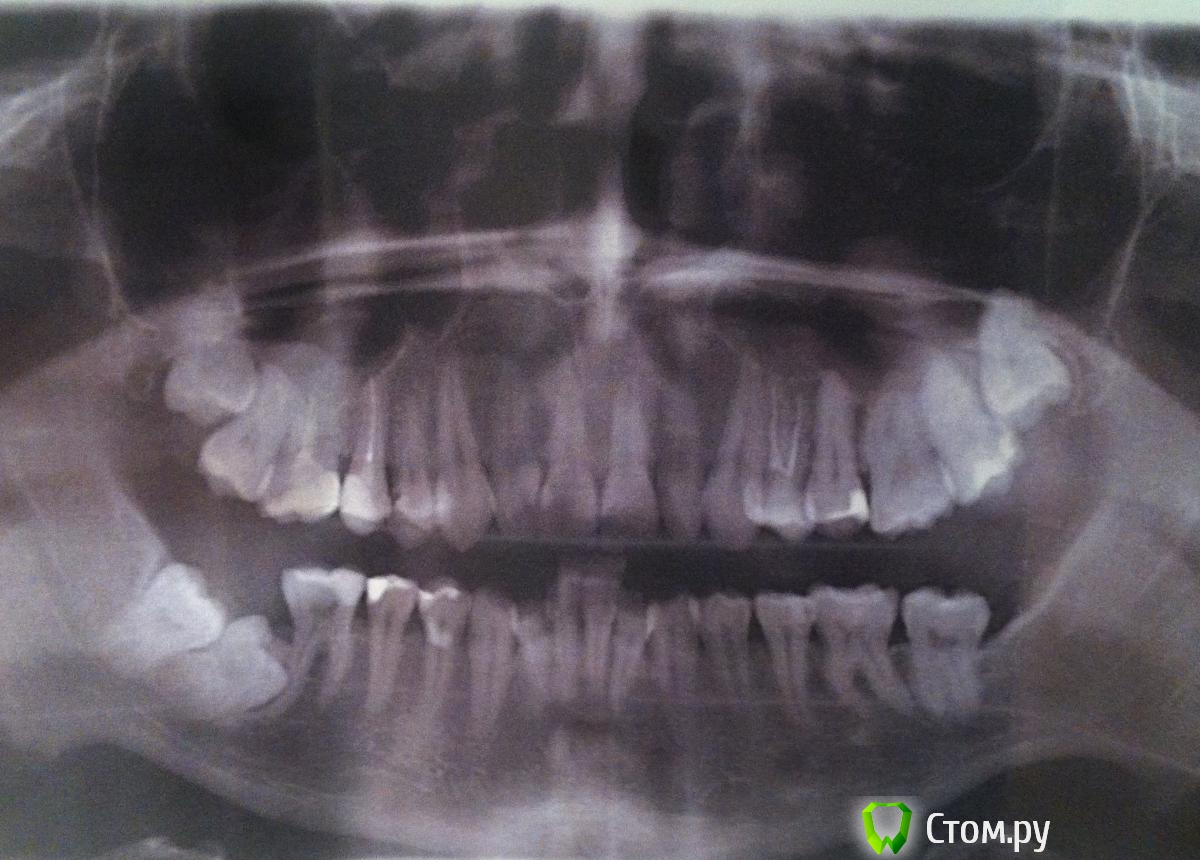

Был у врача и по плану лечения будут удалять единичку на нижней челюсти и ставить брекеты. На верхней челюсти места достаточно и зубы почти ровные, восьмерки пока удалять не будут. На нижней достаточно тесно, по этому будут удалять один зуб и на месте 4х передних зубов стоящих веером поставят 3 зуба в ряд, насколько я понял большого движения остальных зубов тоже не будет.

Меня смущает что 7 и 8 зубы лежищие в десне не предложили удалить. Врач аргументировал это тем что в мои 26 лет 7 зуб выглядит вросшим в челюсть и по этому удалить 8 и поднять 7 малореально. К тому же к ним близко нерв. По этому по плану сначала брекеты а затем спустя пол года уже можно пойти к хирургу и удалять их.

post-40158-0-06872500-1410882489_thumb.jpg

Нужно КТ(компьютерная томограмма) в области "лежащих 7-ки и 8-ки", вообще в таких случаях действительно, уаляют 8-ку и вытаскивают 7-ку, иногда есть есть исключения,

так же необходимо проверить 6-ку в этой области,